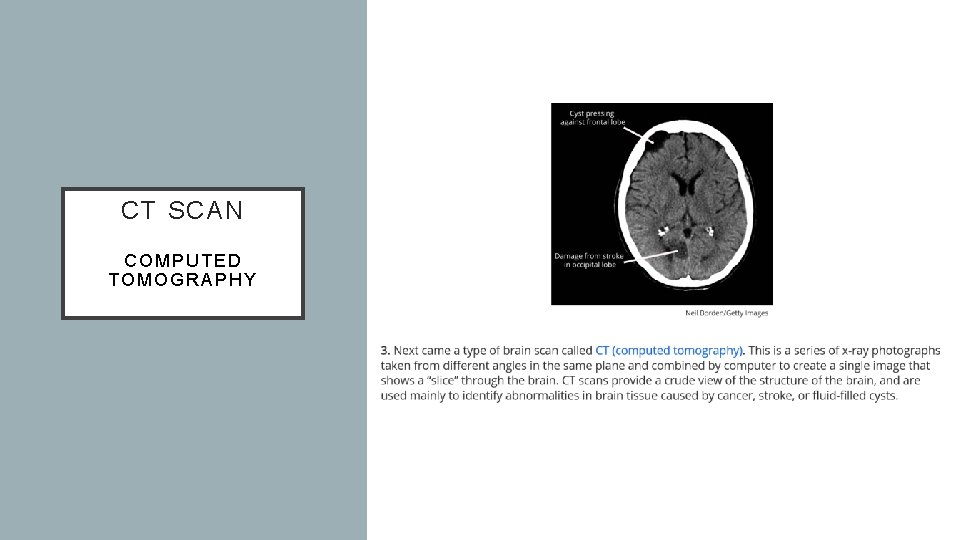

CT SCAN COMPUTED TOMOGRAPHY

Name How does it work? Electroencephalogram (EEG) Electrodes placed on the scalp measure electrical activity in neurons Symptoms of depression and anxiety correlate with increased activity in the right frontal lobe (associated with negative emotion) Magnetic resonance imaging (MRI) People sit or lie down in a chamber that uses magnetic fields and radio waves to provide a map of brain structure People with history of violence tend to have smaller frontal lobes (associated with moral judgement and self control) Computed tomography (CT) X-rays of the head generate images that may locate brain damage Positron emission tomography (PET) Tracks where a temporarily radioactive form of glucose goes while the brain of the person given it performs a given task Magnetoencephalography (MEG) A head coil records magnetic fields from the brain’s natural electrical currents Soldiers with PTSD show stronger magnetic fields in the visual cortex when they view trauma-related images Funtional magnetic resonance imaging (f. MRI) Measures blood flow to brain regions by comparing continuous MRI scans